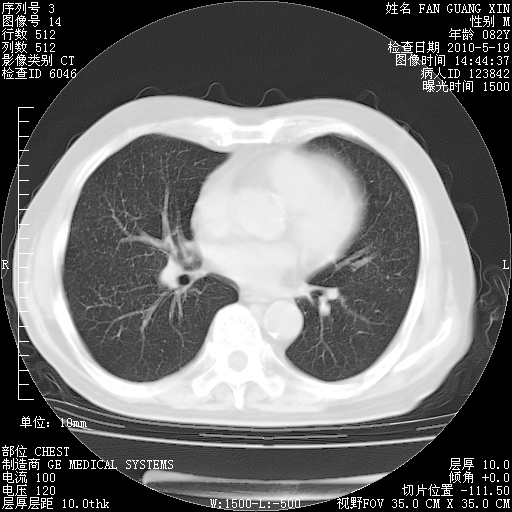

复查肺部CT,明显好转。为什么发热呢?

治疗3周后的肺部CT

治疗3周后的肺部CT纵隔窗